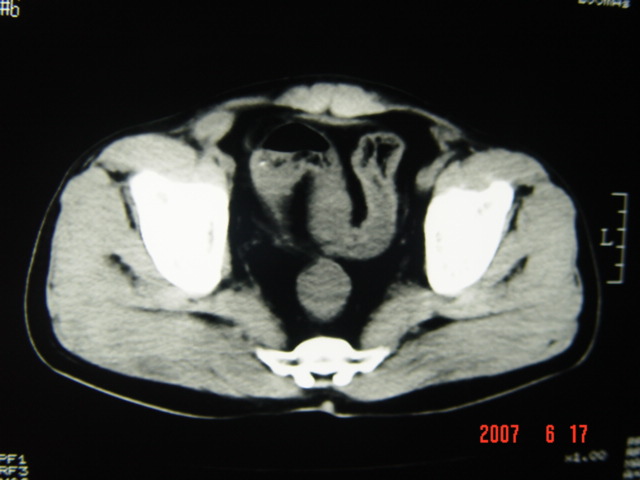

[br][br]以下是引用lkc8963在2007-6-17 13:32:00的发言:[br]完全支持邓主任意见:降/乙交界部占位性病变伴不全梗阻.做个增强或者be可能更好.